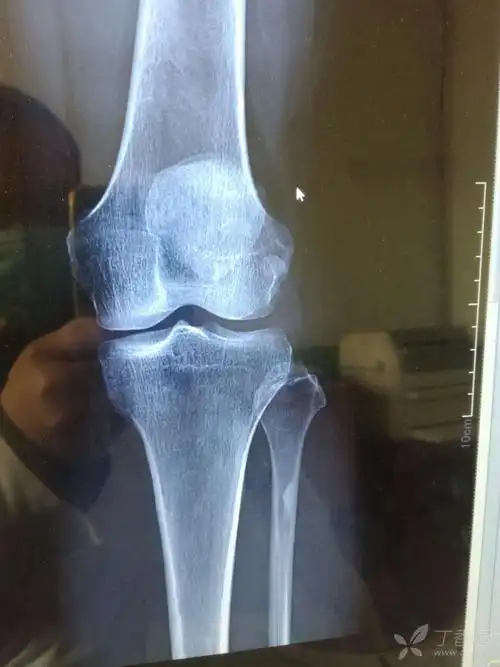

术前x光片

左膝关节正侧位片一例,请各位老师看一下.

征集髌骨骨折x光片按要求提供给予积分

髌骨骨折微创手术一例